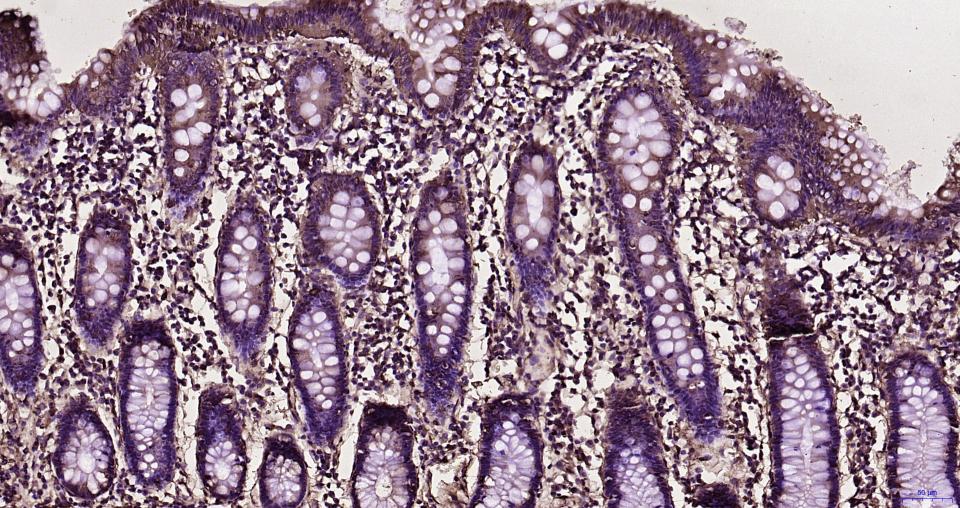

Paraformaldehyde-fixed, paraffin embedded Human colon; Antigen retrieval by boiling in sodium citrate buffer (pH6.0) for 15 min; Antibody incubation with RhoA/B/C Monoclonal Antibody, Unconjugated (bsm-61200R) at 1:200 overnight at 4°C, followed by conjugation to the bs-0295G-HRP and DAB (C-0010) staining.

Paraformaldehyde-fixed, paraffin embedded Mouse colon; Antigen retrieval by boiling in sodium citrate buffer (pH6.0) for 15 min; Antibody incubation with RhoA/B/C Monoclonal Antibody, Unconjugated (bsm-61200R) at 1:200 overnight at 4°C, followed by conjugation to the bs-0295G-HRP and DAB (C-0010) staining.

Paraformaldehyde-fixed, paraffin embedded Rat colon; Antigen retrieval by boiling in sodium citrate buffer (pH6.0) for 15 min; Antibody incubation with RhoA/B/C Monoclonal Antibody, Unconjugated (bsm-61200R) at 1:200 overnight at 4°C, followed by conjugation to the bs-0295G-HRP and DAB (C-0010) staining.